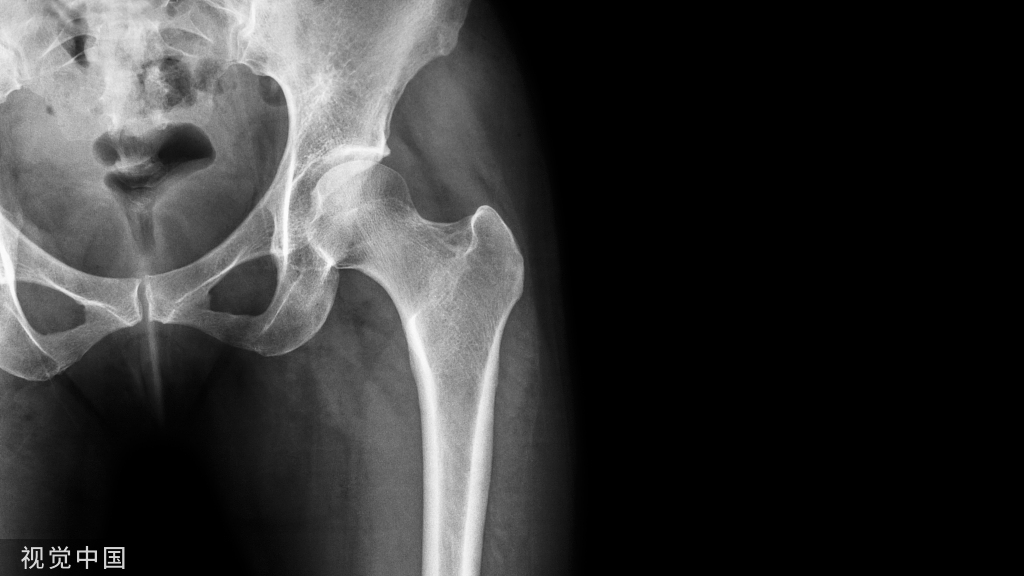

案例分析患者,男,65岁,髋关节疼痛,负重时加重。患者两年前发现左侧臀部及左大腿前部隐约疼痛,1年前屈髋活动受限,现髋关节疼痛,负重时尤甚,不能深蹲,呈避痛步态。MRI提示股骨头缺血性坏死。现入院行全髋置换术。

8.X线检查  含双侧髋关节的骨盆正位片和患侧髋蛙式位片。与健侧进行对比,了解手术关节有无畸形、增生 、对线等影像学的改变,作为重要的手术参考依据。